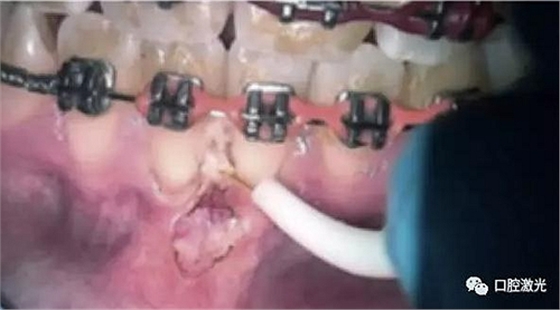

由于藥物或正畸引起的牙齦增生組織去除

表麻下牙齦增生的激光切除即可效果